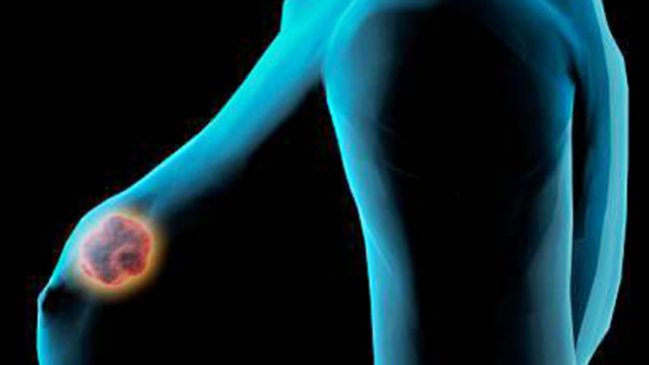

Investigadores españoles han descubierto que la proteína TC21 juega un papel esencial en el desarrollo del cáncer de mama y de la metástasis de pulmón, dos procesos malignos que quedan bloqueados cuando se elimina o inhibe esta proteína.

El estudio preclínico realizado con ratones confirmó que al inhibir esta proteína no solo se impide el crecimiento de los tumores de mama más comunes y de la metástasis de pulmón, sino también de los dos tipos de cáncer de pecho más agresivos: el Her2 y los triples negativos, los subtipos más difíciles de tratar debido a su alta malignidad.

"Hemos demostrado que esta proteína puede ser una buena diana terapéutica para el cáncer de mama porque su inhibición no causa daños al organismo y, en cambio, sí es muy efectiva para frenar los tumores de mama y las metástasis de pulmón", pero a partir de ahora los esfuerzos de la investigación se centrarán en encontrar inhibidores de esta proteína.